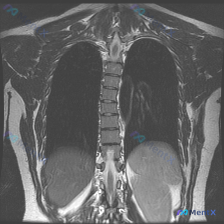

仅有的影像检查是胸部MRI冠状位T2加权像,影像报告的核心发现是:

- 双侧肺野、纵隔、心影未见明显局灶性病变或占位;

- 胸椎序列清晰,椎体形态基本正常,未见明显的形态异常或骨质信号改变;

- 双侧胸廓、软组织结构大致对称。